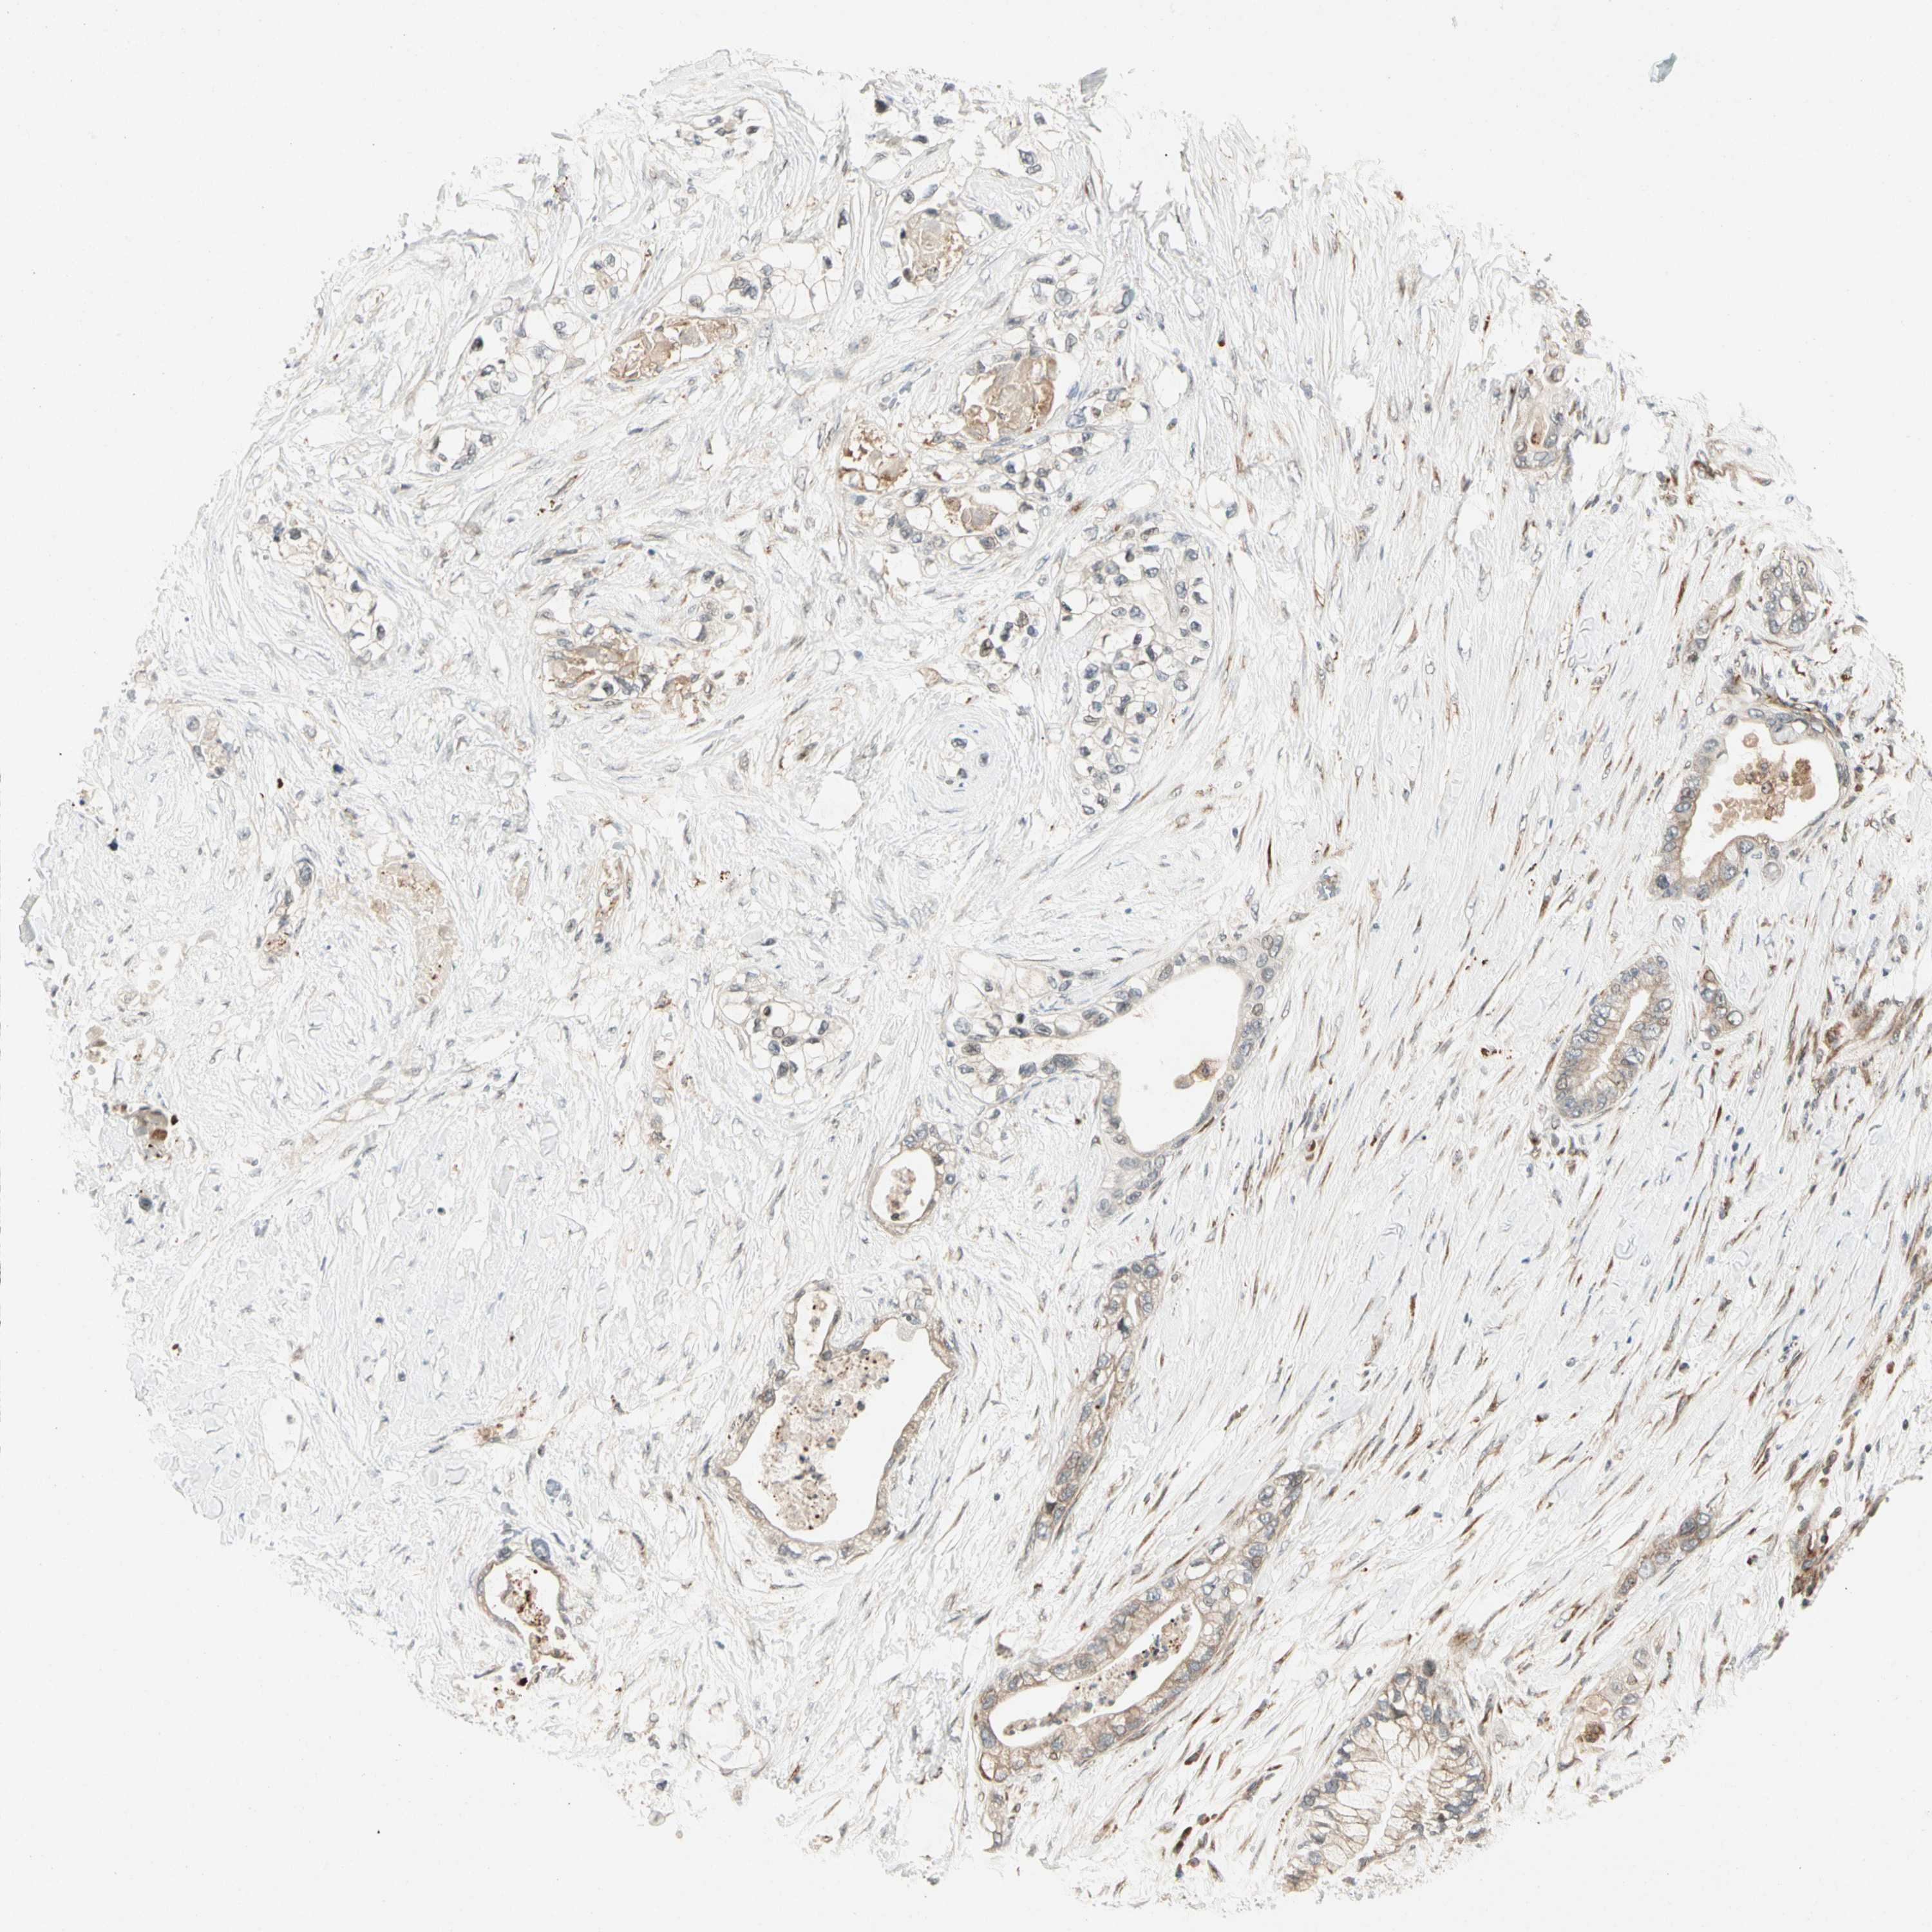

PANCREATIC CANCER - Protein expressioni

A mouse-over function shows sample information and annotation data. Click on an image to view it in a full screen mode. Samples can be filtered based on level of antibody staining by selecting one or several of the following categories: high, medium, low and not detected. The assay and annotation is described here.

Note that samples used for immunohistochemistry by the Human Protein Atlas do not correspond to samples in the TCGA dataset.

Antibody stainingi

Antibody staining in the annotated cell types in the current human tissue is reported as not detected, low, medium, or high, based on conventional immunohistochemistry profiling in selected tissues. This score is based on the combination of the staining intensity and fraction of stained cells.

Each image is clickable and will lead to virtual microscopy that enables deeper exploration of all samples and also displays staining intensity scores, fraction scores and subcellular localization as well as patient and tissue information for each sample.

Antibody HPA007859

Staining

High

Medium

Low

Not detected

Intensity

Strong

Moderate

Weak

Negative

Quantity

>75%

75%-25%

<25%

None

Location

Nuclear

Cytoplasmic/membranous

Cytoplasmic/membranous,nuclear

Adenocarcinoma, NOS